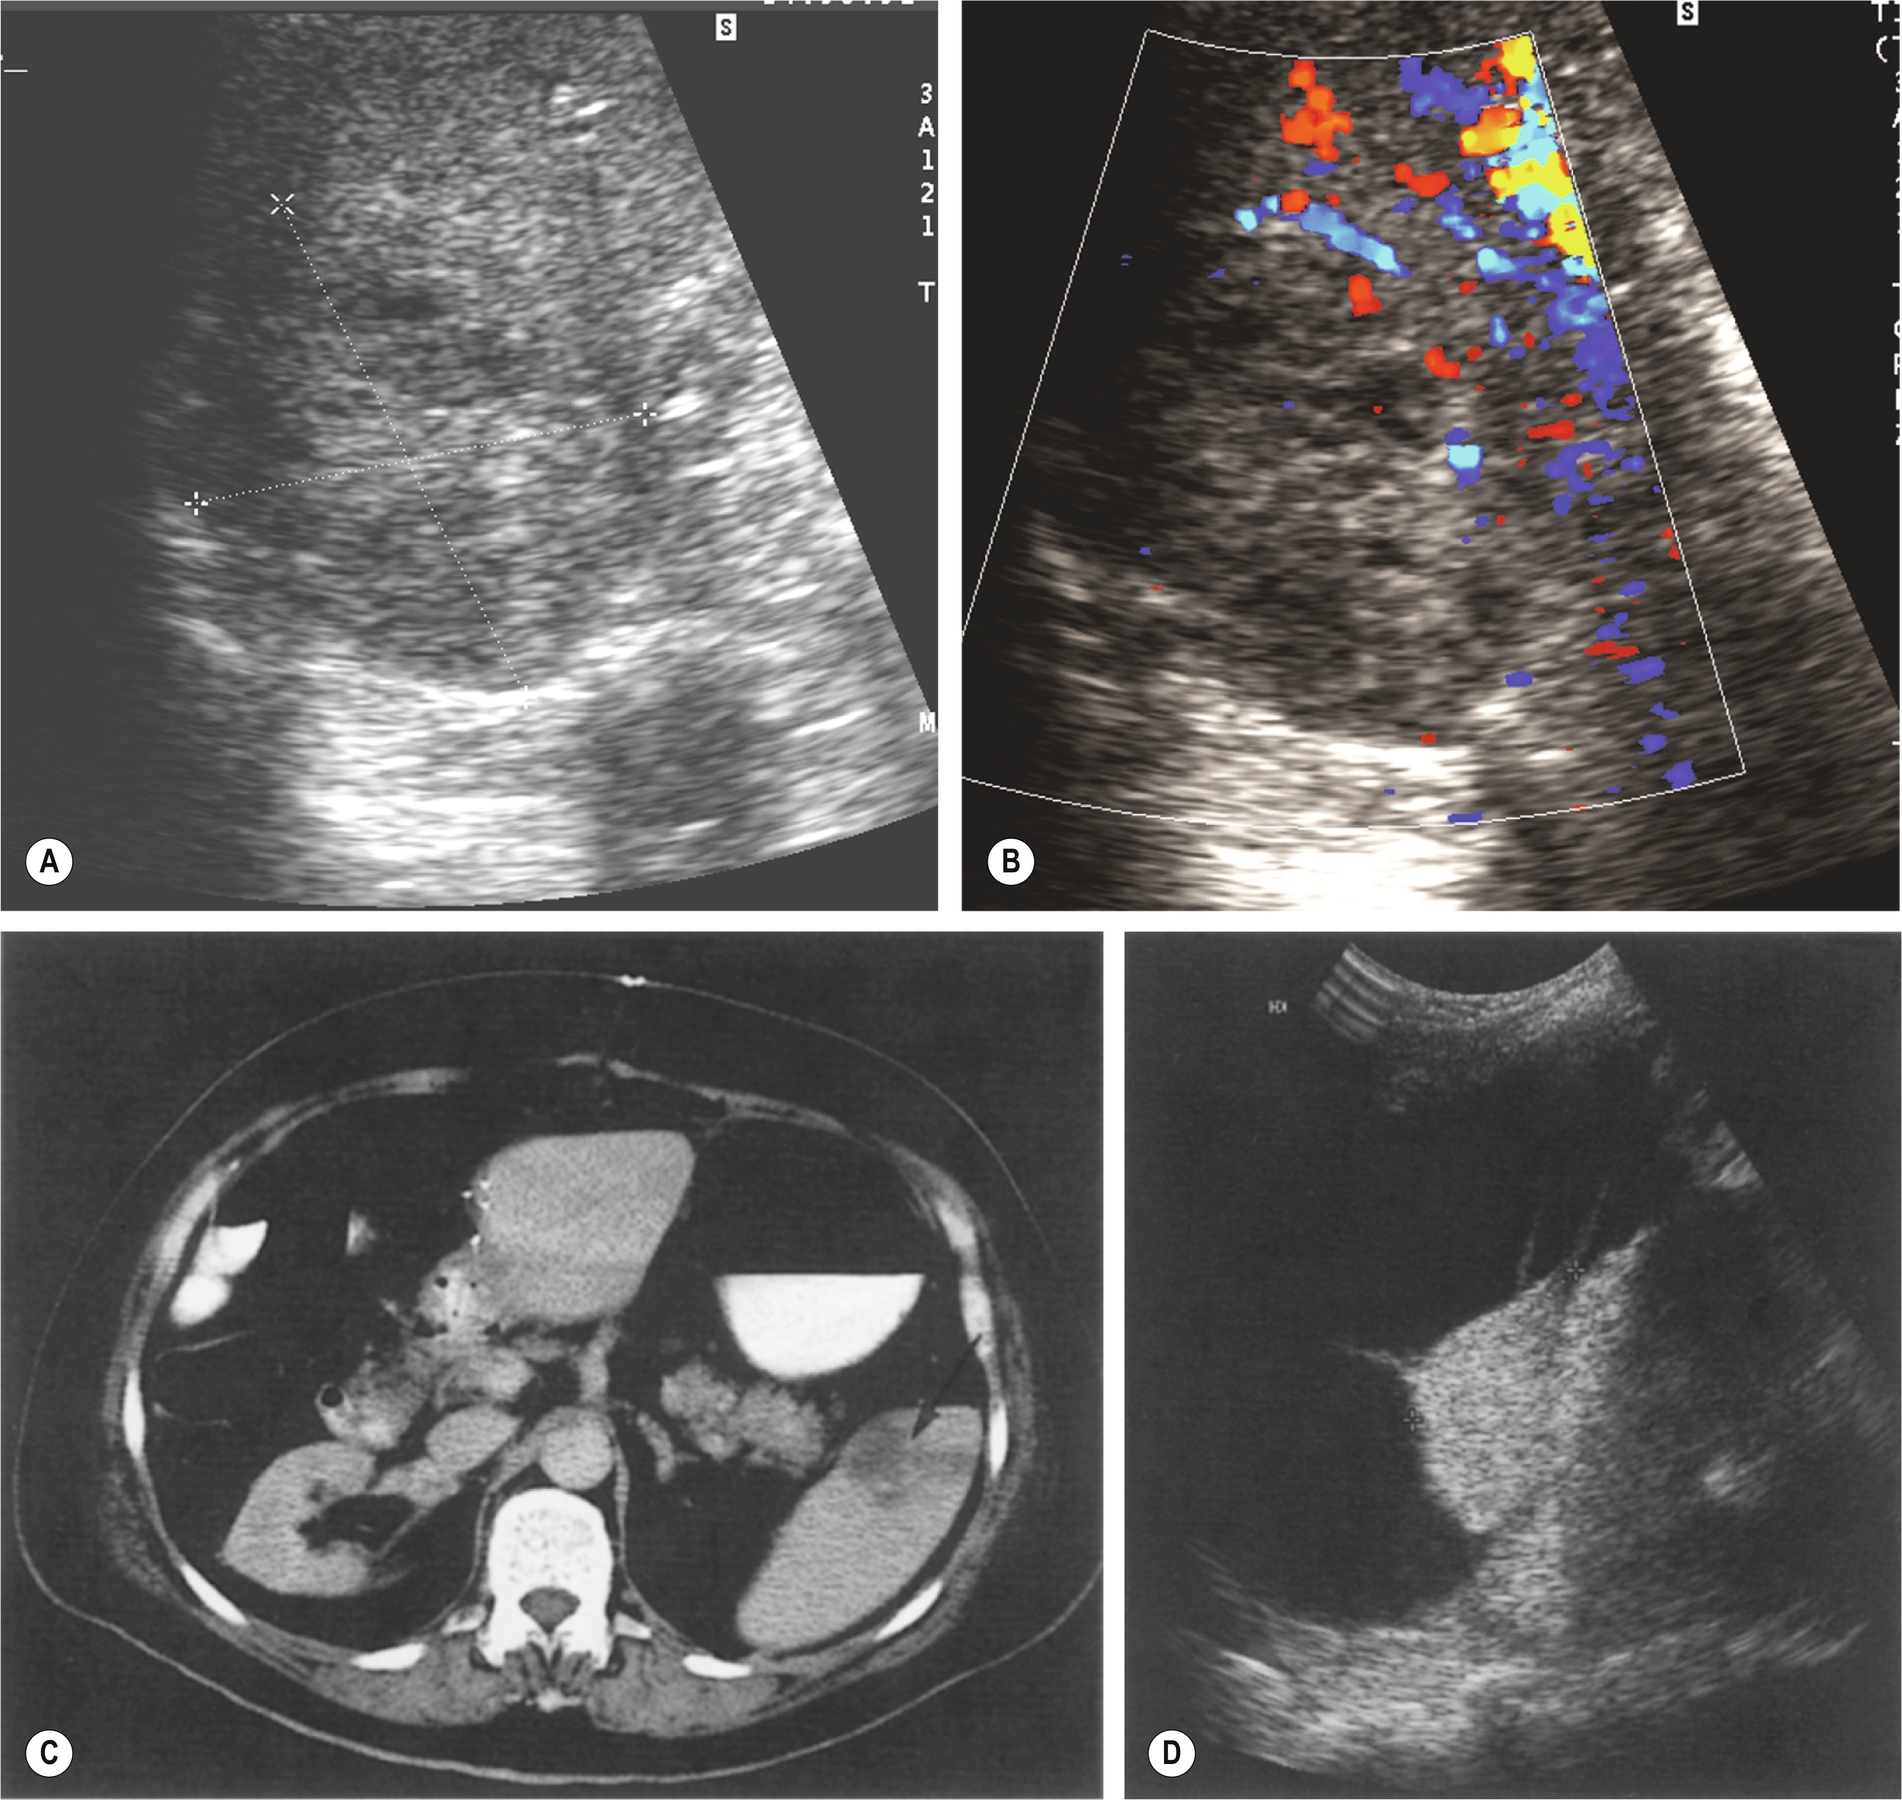

As with liver metastases, the ultrasound appearances vary enormously, ranging from hypo- to hyperechogenic or of a mixed pattern (Fig. 5.4). They may be solitary, multiple, or diffusely infiltrative, giving a coarse echo pattern. Metastases are usually solid in appearance. When cystic components are seen, this could indicate central necrosis or that the primary tumor is mucinous in nature (e.g., ovarian carcinoma).13

Splenic cysts have a relatively low incidence but are nevertheless the most common benign mass found in the spleen (Fig. 5.4D). Typically, cysts are rounded, with a thin wall with no internal echoes and posterior enhancement; occasionally thin septations may be seen, and also debris because of hemorrhage. Splenic cysts may occasionally be associated with autosomal dominant polycystic disease.

Splenic infarction is most commonly associated with sickle cell anemia, hematological malignancies, thrombophilia, and emboli because of endocarditis. It has also been reported more recently as a complication of hepatocellular carcinoma embolization.16 It usually results from thrombosis of one or more of the splenic artery branches. Because the spleen is supplied by both the splenic and gastric arteries, infarction tends to be segmental rather than global. Patients may present with LUQ pain, but not invariably.

Initially, the area of infarction is hypoechoic and usually wedge-shaped, solitary, and extending to the periphery of the spleen (Fig. 5.7). In the acute phase of infarction, B-mode ultrasound is not often useful, only identifying 50% of infarctions resulting in a high false-negative rate. The lesion may decrease in time and gradually fibrose, becoming hyperechoic. If the infarction is large, it may demonstrate reduced Doppler perfusion when compared to the normal splenic tissue, and CEUS may be particularly helpful in outlining the area of non-perfusion, allowing a definitive diagnosis and is represented as a triangular or slightly rounded area with the base extending to the splenic capsule. In rare cases of total splenic infarction (Fig. 5.7D), because of occlusion of the proximal main splenic artery, gray-scale sonographic appearances may be normal in the early stages.

CT should be performed as the first imaging step in patients with blunt trauma, as it can also detect laceration to the gastrointestinal tract and other extra-visceral injury as well as assess the blood supply within the spleen (Fig. 5.8).